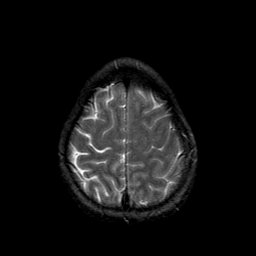

Metastatic bronchogenic carcinoma: T2-weighted MR -- Slice #19

[Home][Help][Clinical] Slice 19